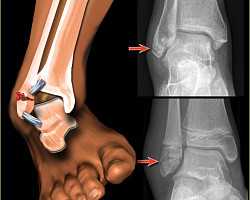

Выбор оперативного доступа при внутрисуставных переломах голеностопного сустава: обзор

В статье приведен анализ рациональности выбора оперативного доступа к голеностопному суставу при хирургических вмешательствах с учетом показаний, сложности выполнения и операционных осложнений. Также проведен разбор современных методик выполнения оперативных доступов.

Ключевые слова: оперативный доступ, голеностопный сустав, внутрисуставные переломы, осложнения .

В литературе описано около 20 оперативных доступов к данной зоне, которые могут быть продлены в проксимальном или дистальном направлении при необходимости. Наиболее применимы медиальный, латеральный доступы и их комбинации ввиду их соответствия следующим условиям: удобство выполнения оперативного маневра хирургом, обеспечение кратчайшего расстояния до очага поражения, быстрота и техническая простота выполнения, максимальное щажение окружающих тканей и минимизация интраоперационных, ранних и поздних послеоперационных осложнений [2].

2. Медиальный доступ

Стандартный медиальный доступ представляет собой продольный разрез слегка кпереди или кзади от лодыжки.

— Для выявления, мобилизации и защиты нервно-сосудистой системы используется тупое рассечение.

— Следует защищать подкожную вену и нерв, так как при повреждении последнего возможно образование неврином.

- Для оперативного лечения повреждений медиальной лодыжки наиболее предпочтителен медиальный доступ, ввиду его соответствия необходимым требованиям.

Для доступа к зоне перелома использовались стандартные хирургические доступы. Для доступа к латеральной лодыжке использовался доступ Кохера, для доступа к медиальной лодыжке применяли классический медиальный доступ.